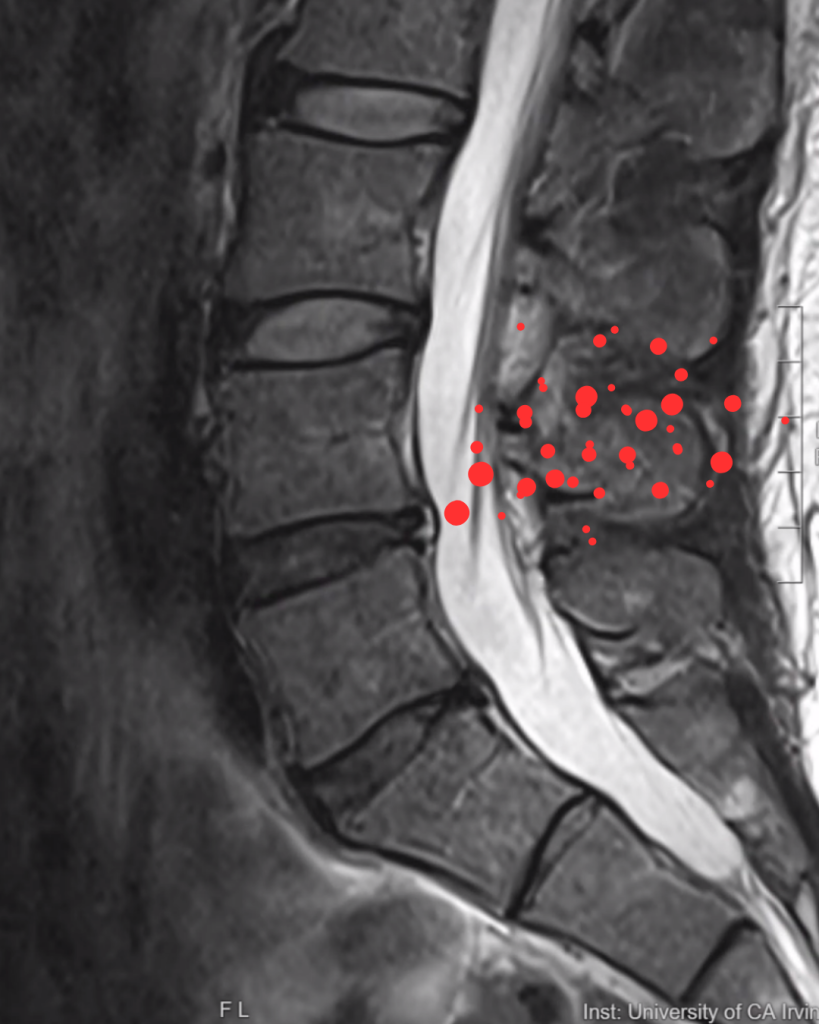

Does Size Matter When It Comes to Disc Herniations?

The truth is… the size of a herniated disc on an MRI is only part of the story.

Why Size Alone Doesn’t Tell the Whole Story

It’s easy to assume that a larger herniation automatically means worse symptoms — but that’s not always the case. Here’s why:

• Position is everything. Even a small herniation can cause severe nerve pain if it presses directly on a nerve root or the spinal cord.

• Your body’s response matters. Some herniations cause significant inflammation, which can trigger pain, numbness, or weakness even without major compression.

• Nerve sensitivity varies. Not all nerves react the same way to pressure — some can tolerate more compression without symptoms.

• Your lifestyle plays a role. Active people often have stronger core and back muscles that help stabilize the spine, which can make it easier to manage a disc herniation and sometimes experience less pain. In contrast, people who are more sedentary may lack that extra muscle support, so even a small herniation can feel more painful or limiting.

Understanding which type you have is just as important as knowing its size.

The size of your disc herniation is just one piece of the puzzle. The real question is: How is it affecting your life? Your symptoms, activity level, and personal goals are all key factors in deciding the best treatment plan.